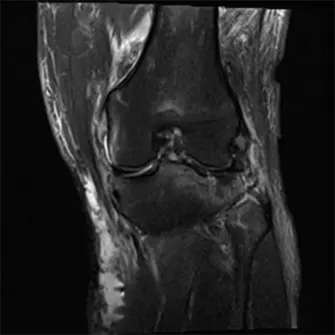

صورة بالأشعة السينية الأولية للركبة اليسرى تُظهر كسرًا مفتتًا ثنائي اللقمة في هضبة الظنبوب مع انخفاض كبير في السطح المفصلي وانفصال بين الجزء المفصلي وجسم العظم، بما يتوافق مع إصابة من النوع السادس حسب تصنيف شاتزكر.

الشكل 1: صورة بالأشعة السينية الأولية للركبة اليسرى تُظهر كسرًا مفتتًا ثنائي اللقمة في هضبة الظنبوب مع انخفاض كبير في السطح المفصلي وانفصال بين الجزء المفصلي وجسم العظم، بما يتوافق مع إصابة من النوع السادس حسب تصنيف شاتزكر.